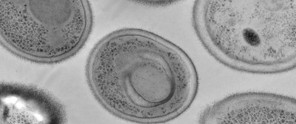

Microscopische afbeelding van cellen met duidelijke celwanden en herkenbare organellen in grijstinten.

Omdat Candida auris makkelijk resistentie ontwikkelt en er weinig verschillende antischimmelmiddelen bestaan, zijn artsen snel uitbehandeld. Nieuw onderzoek van KU Leuven toont aan dat resistentie tegen één therapie de werkzaamheid van een andere net kan verhogen. Daardoor kan de gevreesde resistentie gebruikt worden tegen deze gevaarlijke schimmelinfectie. De onderzoeksresultaten worden vandaag gepubliceerd in Nature Microbiology.

Wist je dat we op één dag tot tien miljard schimmelsporen inademen? Gelukkig zijn de meeste schimmels ongevaarlijk en zelfs essentieel voor een gezond lichaam. Toch is er één schimmel die door de Wereldgezondheidsorganisatie (WHO) als eerste schimmel het label ‘topurgent’ kreeg. Candida auris is een nieuwe soort die voor het eerst werd beschreven in 2009. Hij kan, vooral in personen met een verzwakt immuunsysteem, erg gevaarlijk zijn met een sterftecijfer van 30 tot 70%. Het grootste probleem bij zulke Candida auris-infecties, is dat hij erg snel resistent wordt aan het kleine arsenaal van antischimmelgeneesmiddelen.